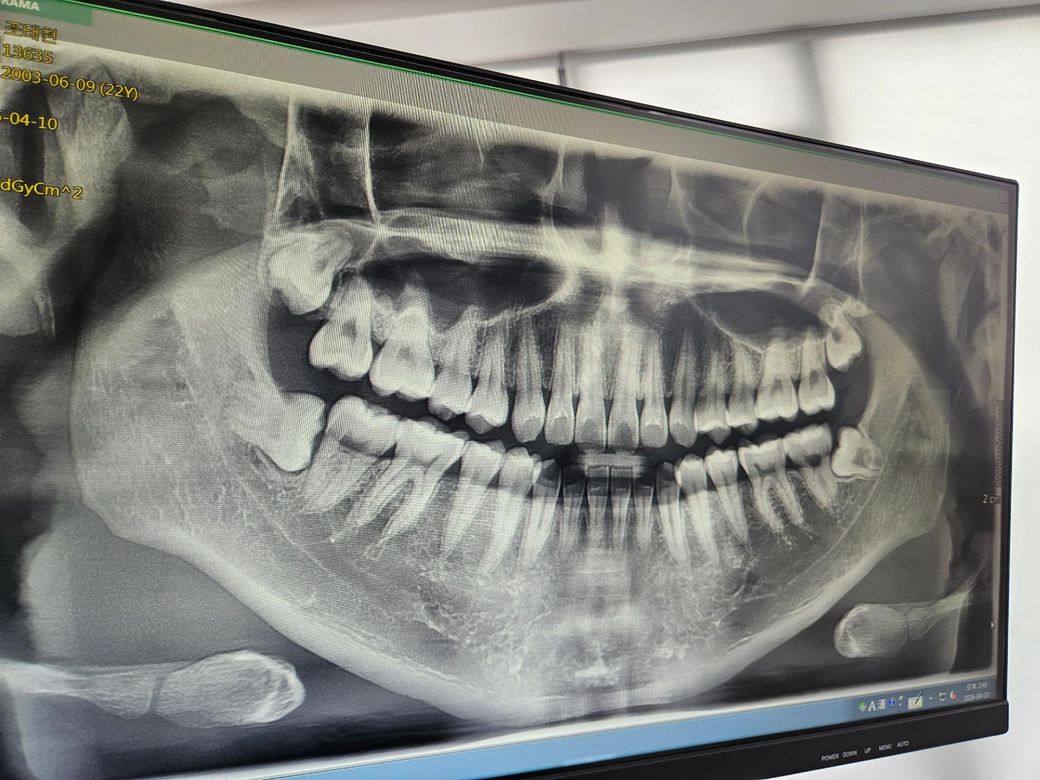

엑스레이상 왼쪽아래는 신경을 건든다고 발치 했는데 나머지 부분이 대한 의견이 궁금합니다. 왼쪽아래를 제외한 사랑니는 잇몸으로 다 가려져있어 육안으론 보이지 않습니다.

나머지 남은 사랑니는 파노라마상 꼭 빼야 할 상황은 아닌 것 같습니다. 신경을 건드린다고 꼭 빼야하는 것도 아니고요.

일딘 아래쪽 사랑니는 양쪽 모두 누워있어 발치하시는게 좋겠습니다만, 엑스레이상 양쪽 모두 신경과 맞닿아있는 것으로 보여 일단 3차원적인 영상판독이 필요해보입니다. 윗쪽 사랑니는 반드시 뽑아야할 필요는 없으나 음식을 저작하는 기능을 전혀 하지 않고, 깊숙한 곳에 위치하고 있어 양치가 어렵기 때문에 추후 문제를 일으킬 가능성이 높으므로 가능하면 뽑기 쉬울 때 미리 뽑는것이 좋다고 생각합니다. 나이가 들 수록 뼈와 단단하게 붙어버리기도 하고, 충치나 염증이 생기면 더 뽑기가 힘들어지기 때문에 가능하면 미리 뽑아주는게 더 좋습니다. 아래 사랑니는 꼭 ct찍어보시고 전문의의 소견에 따라 결정하시는게 좋겠습니다.